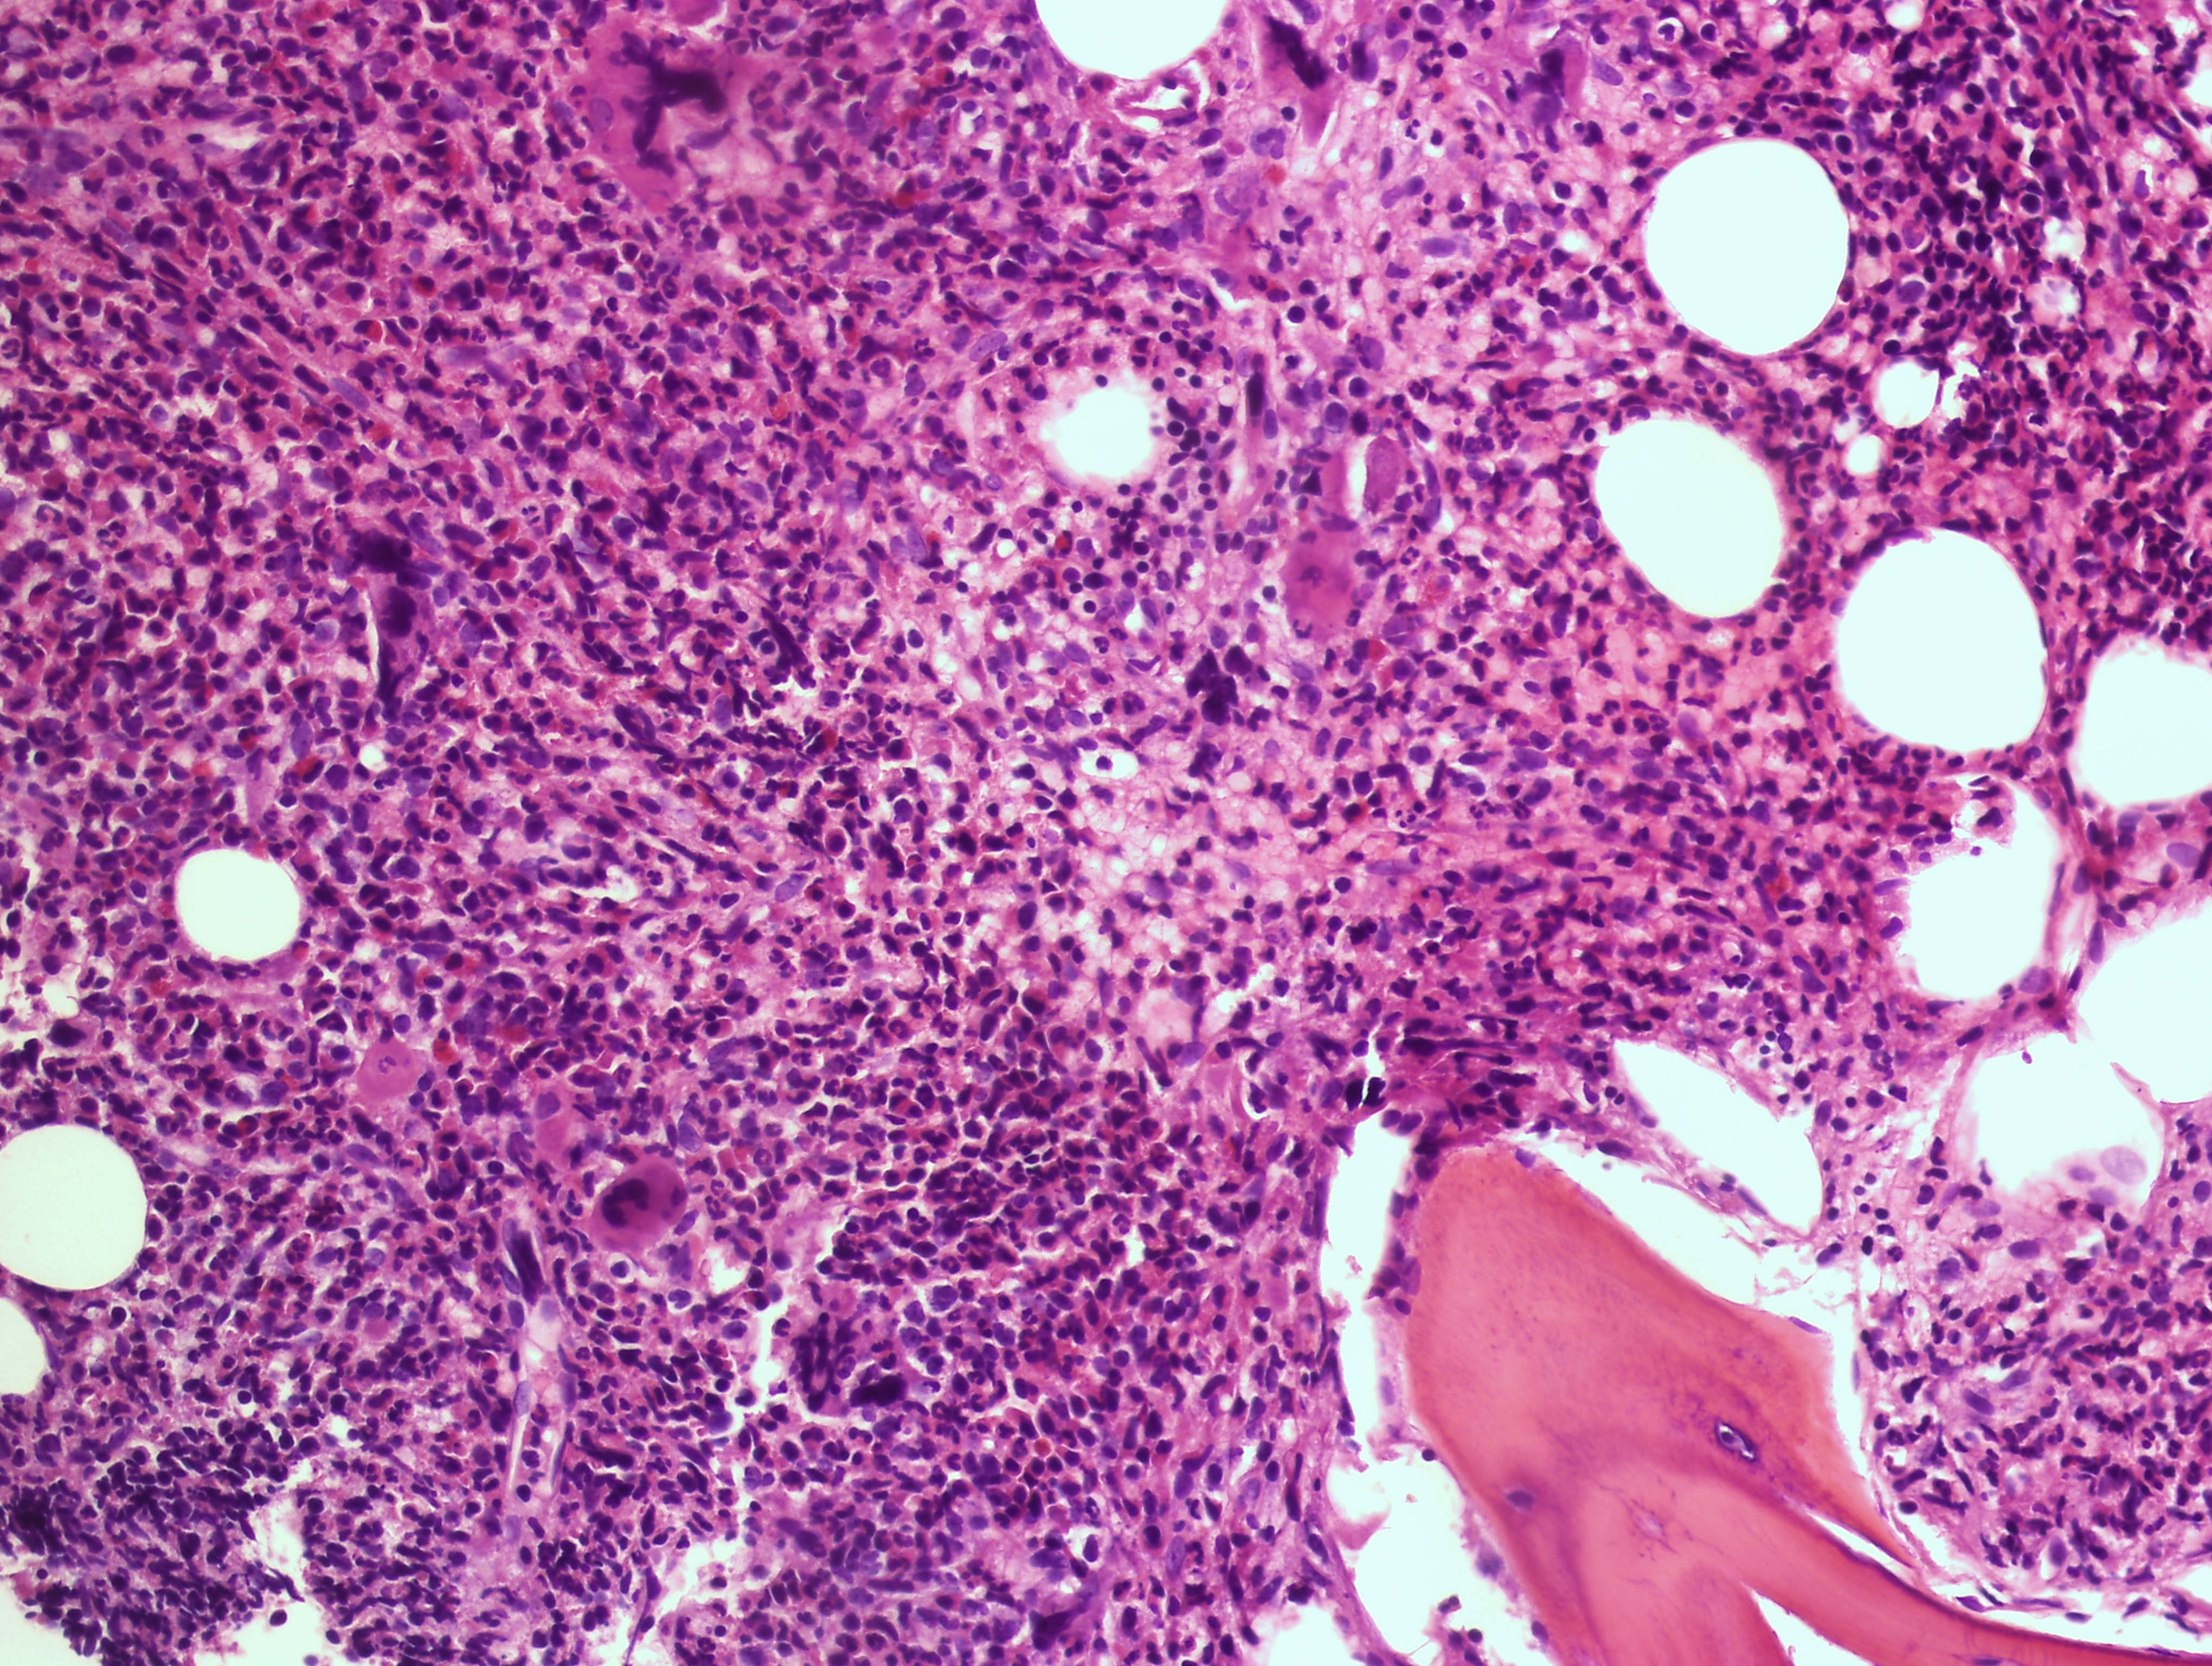

Per diagnosticar-la és indispensable fer una biòpsia de medul·la òssia que, juntament amb l'analítica, permetrà determinar els factors de risc de progressió de la malaltia, que guiaran el tractament.

Es caracteritza per fibrosi de la medul·la òssia, defecte progressiu de la producció de les cèl·lules de la sang i una marcada presència de símptomes constitucionals, a més de l'augment de la mida de la melsa i del fetge que proven de compensar la producció de glòbuls vermells.

La mielofibrosi està inclosa en el grup de malalties mieloproliferatives cròniques, pot ser d'aparició nova (primària) o posterior a la policitèmia vera o la trombocitèmia essencial.